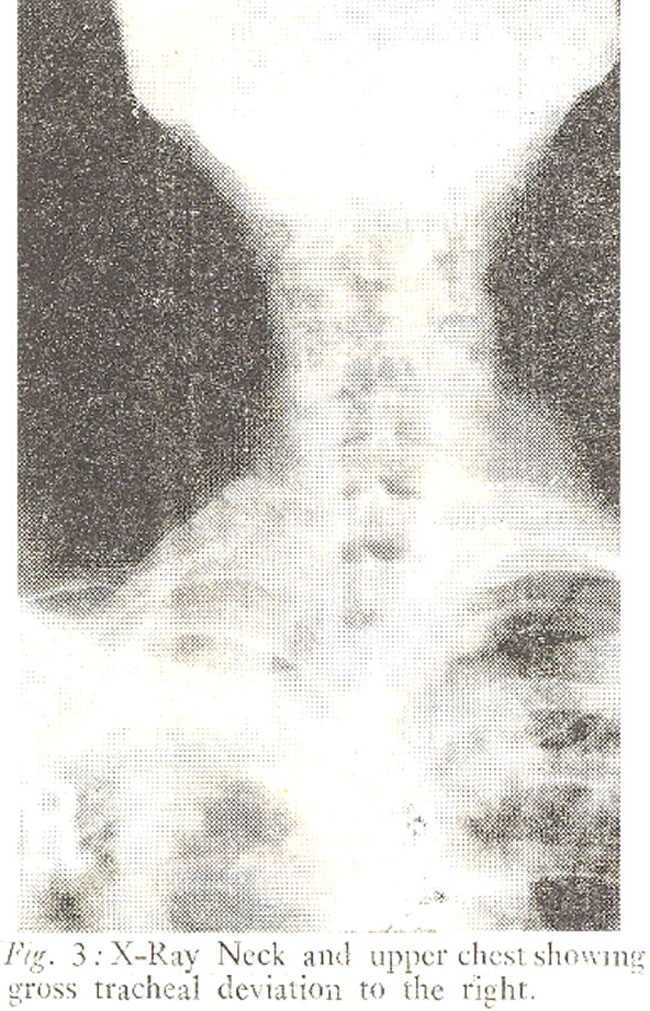

Clinical examination of the larynx showed a tumour arising from the epiglottis, occupying mainly the right half of the cartilage. The rest of the epiglottis was oedematous, the aryepig-lottic folds ventricular bands and vocal cords were hyperaemic, the right cord showing restricted movements on phonation. Two Right Upper deep cervical nodes were palpable and mobile. He was admitted for further examination and investigations. X-Ray neck lateral view-showed swelling of the epiglottis. X-Ray chest showed gross fibrotic changes on the right side, with obvious deviation of the trachea;. Blood examination revealed Hb 11.9G%, TLC 5,300 with a normal differential count and ESR 30mm 1 st hour. Sputum could not be tested and a direc laryngoscopy complied with the clinical diagnosis. The histological examination of the biopsy confirmed the diagnosis of Tuberculous Granuloma.

The presentation of the case has resembled carcinoma with a short history of progressive hoarseness and dysphagia. Other authors have emphasised laryngeal tuberculosis mimicking carcinoma (Bull, 1966; Hunter, 1981). In their cases the lesions were noted mostly on the vocal cords and ventricular bands and were associated with moderate to advanced pulmonary tuberculosis. In the present case histological examination of biopsy material was necessary to confirm the diagnosis. X-Ray chest showed extensive fibrotic changes but no active pulmonary lesion. Sputum could not be obtained for examination. This exemplifies the difficulty in early diagnosis of laryngeal tuberculosis in the general population.